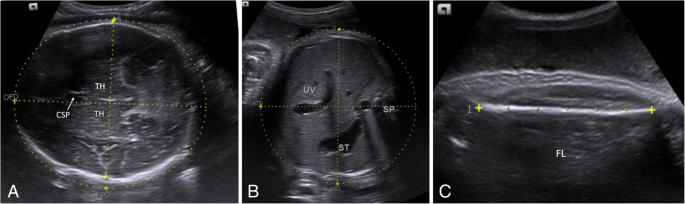

- Fetal biometric measurements, including biparietal diameter (BPD), femur length (FL), abdominal (AC), and head circumferences (HC)

The fetal anatomy scan offers an in-depth examination of the fetus, placenta, and maternal anatomy, focusing on:

- General Principles: The primary objectives are to screen for fetal anomalies and confirm or adjust gestational age estimations.